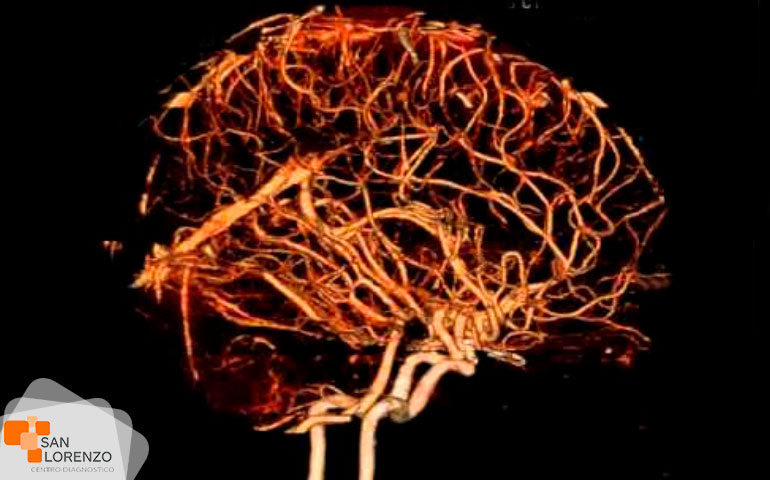

Cuando su médico especialista requiera una mejor visualización de los órganos, o estructuras internas normales o con lesiones, puede solicitar su examen con medio de contraste, éstos son sustancias indispensables para distinguir con mayor claridad áreas del cuerpo o tejidos circundantes que ayuden a diagnosticar condiciones médicas relacionadas con órganos específicos, vasos sanguíneos, o tejidos.

Algunos de los exámenes relacionados con medios de contraste son: Angiotac, Urotac, TAC de abdomen y pelvis, TAC de cerebro en lo que se solicite contraste, y todas aquellas Resonancias magnéticas contrastadas.

¿Para qué tipos de exámenes se aplica la medición de la creatinina? ¿Podemos mencionar los exámenes? Todos los exámenes de RM, TAC que requieran contraste tal como los mencionados anteriormente: Angiotac, Urotac, TAC de abdomen y pelvis, TAC de cerebro en lo que se solicite contraste y todas aquellas Resonancias magnéticas contrastadas.